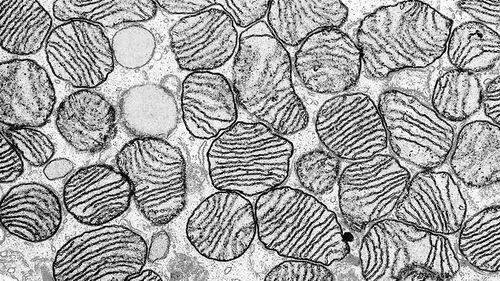

1. 线粒体DNA(mtDNA)突变治疗策略。

由于线粒体基因组缺乏天然的DNA修复和重组机制,基因编辑产生的直接DNA改变对其是没有作用的,而GGT中的一种方法即线粒体替代治疗(mitochondrial replacement therapy , MRT)通过用捐赠者的未突变mtDNA替代突变携带者卵母细胞中的突变mtDNA,从而实现安全地抑制有害的线粒体基因突变从母体转移给婴儿。值得注意的是,MRT过程中仍会有一小部分(1-4%)的母系突变mtDNA残留在卵母细胞或是胚胎中,虽然这些微量突变不足以致病,但是,在胚胎移植后期和胎儿发育过程中其选择性扩增和快速逆转为同质母体mtDNA仍是潜在的安全隐患。